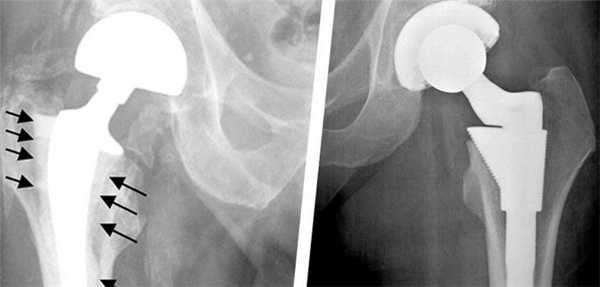

Инфекционное осложнение и установка дополнительного расширителя.

Вероятность развития осложнений не превышает 5%, из них интраоперационные последствия практически не встречаются. Преобладают такие осложнения, как вывихи компонентов имплантата и перипротезные переломы, которые чаще возникают из-за несоблюдения пациентом назначенного ортопедического режима.